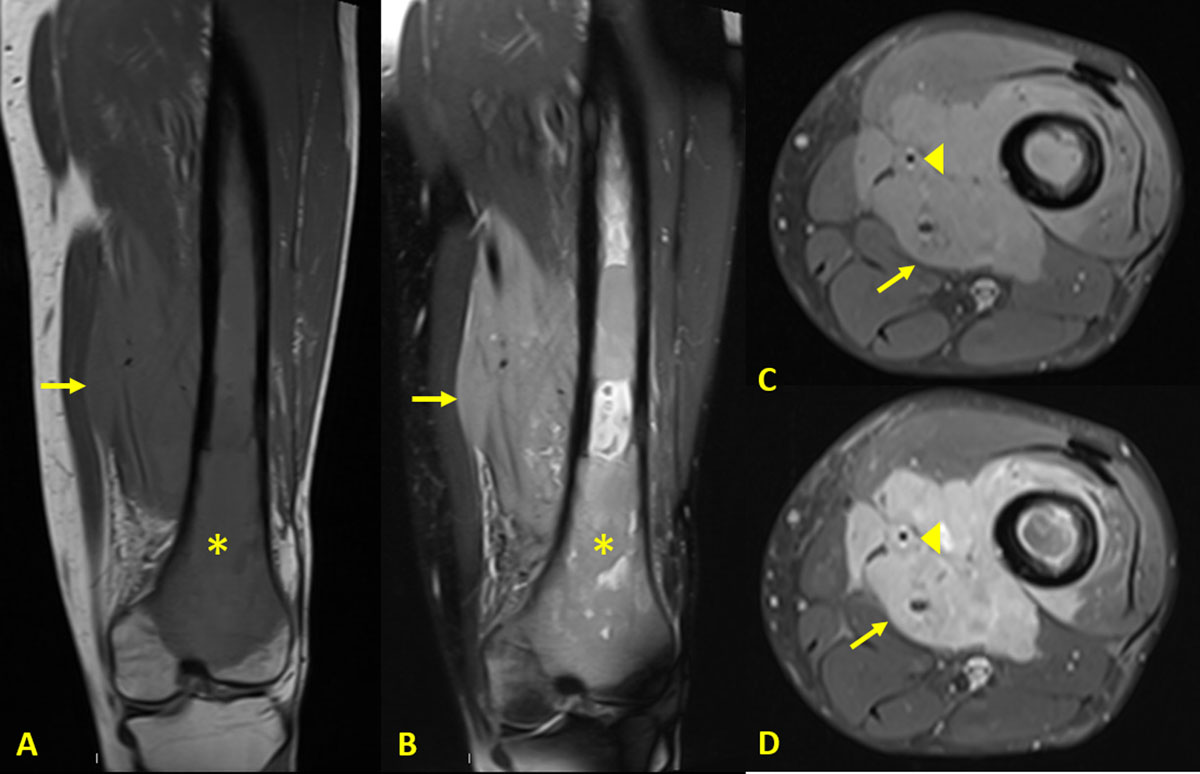

Magnetic resonance imaging (MRI) revealed a large soft tissue mass infiltrating the thigh’s muscles (arrows in Figure 3) and the neuro-vascular bundle (arrowheads in Figure 3C and 3D). It had an intermediate signal on T1-weighted images (T1WI) (Figure 3A and 3C), high signal on DP-weighted images with fat saturation (FS DPWI) (Figure 3B) and enhanced after contrast injection (Figure 3D). The medulla of the femur was hypointense on T1WI (asterisk in Figure 3A) and hyperintense on FS DPWI (asterisk in Figure 3B). There was no cortical disruption.

Figure 3

MRI of the knee showing a large soft tissue mass infiltrating the thigh’s muscles.